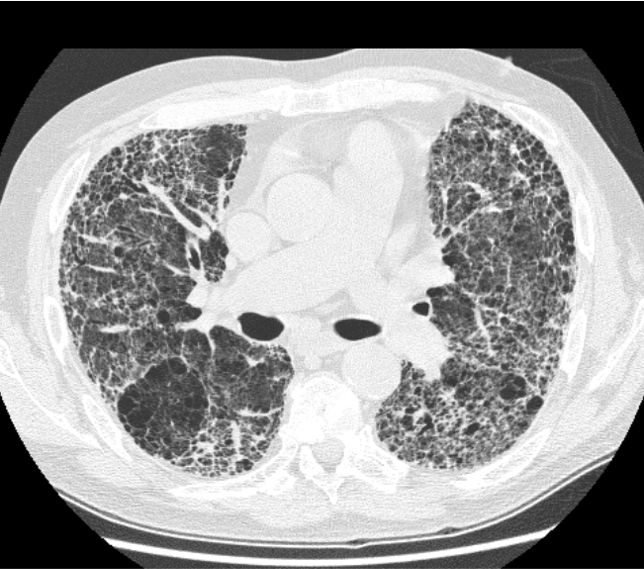

CT scans are volumetric, represented as a stack of 2D images (“slices”). An ORIGINAL CT series will consist of axial slices that are not cropped, e.g.:

A CT scan slice in the layout expected of ORIGINAL CT series. This CT slice shows extensive pulmonary fibrosis. It is from Wikipedia and released under a Creative Commons license.